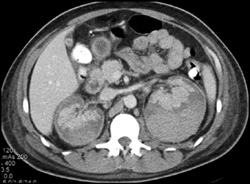

Delayed Nephrogram Left Kidney